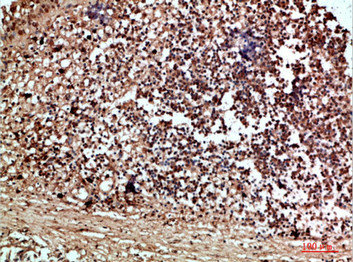

IHC (Immunohiostchemistry)

(Immunohistochemical analysis of paraffin-embedded human-thyroid, antibody was diluted at 1:200)